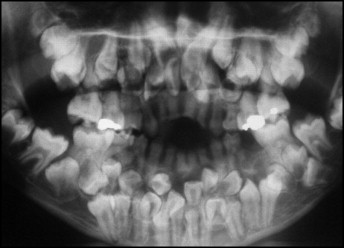

Qua khám trong miệng, các bác sĩ ghi nhận chỉ có 5 răng vĩnh viễn đã mọc. Trong khi đó, các răng sữa vẫn còn tồn tại khá nhiều. Nhằm đánh giá toàn diện hơn tình trạng răng miệng của bệnh nhi, các bác sĩ đã chỉ định chụp phim toàn cảnh và phim sọ nghiêng. Kết quả phim cho thấy một bất thường nghiêm trọng: sự hiện diện của rất nhiều răng thừa.

Hình chụp X-quang của bệnh nhi

Cụ thể, kết quả chụp đã cho thấy bệnh nhân có tổng cộng 81 chiếc răng, bao gồm: 18 răng sữa, 32 răng vĩnh viễn và 31 răng thừa. Các hình ảnh cũng cho thấy nhiều răng có hình thể bất thường khiến việc phân biệt giữa răng thường và răng thừa trở nên vô cùng khó khăn.